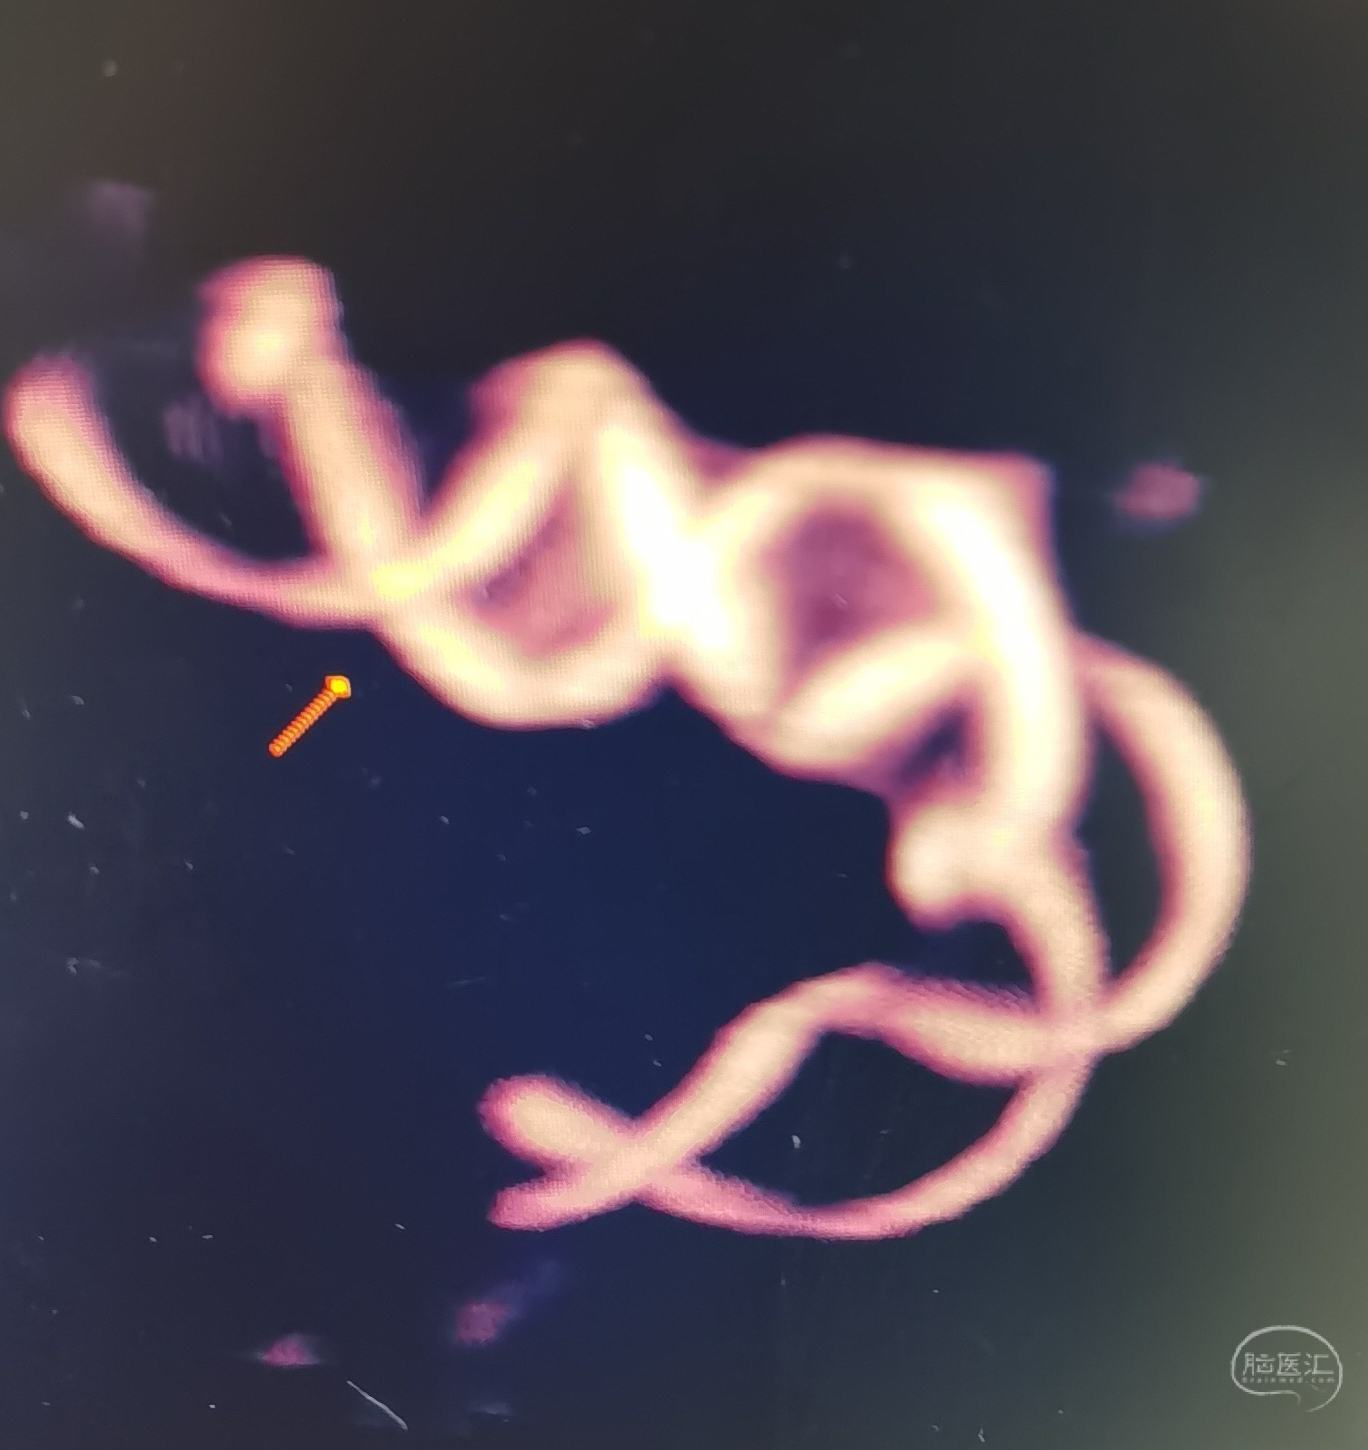

DSA示左侧后交通微小动脉瘤,起自后交通,血泡样。

3D示动脉瘤大小约1.36✘1.40mm

胚胎型后交通动脉。

压颈DSA造影示左侧P1缺如。

支架Atlas4.0×21mm辅助栓塞动脉瘤,支架放置后交通动脉。

target1.0×3.0,1.0×2.0mm两枚coiling.

动脉瘤栓塞良好。

后交通及载瘤动脉通畅。